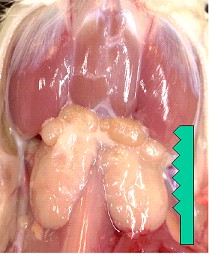

الغدد تحت اللسان sublingual glands هم الغدد اللعابية في الفم.

الغدد تحت اللسانية sublingual gland وهي أصغر الغدد اللعابية حجماً بين الغدد اللعابية الثلاث الرئيسية، تقع أسفل مخاط قاعدة الفم. تحتوي على أسناخ مصلية و كثير من الأسناخ المخاطية. وتقع داخل فجوة في عظم الفك السفلي.